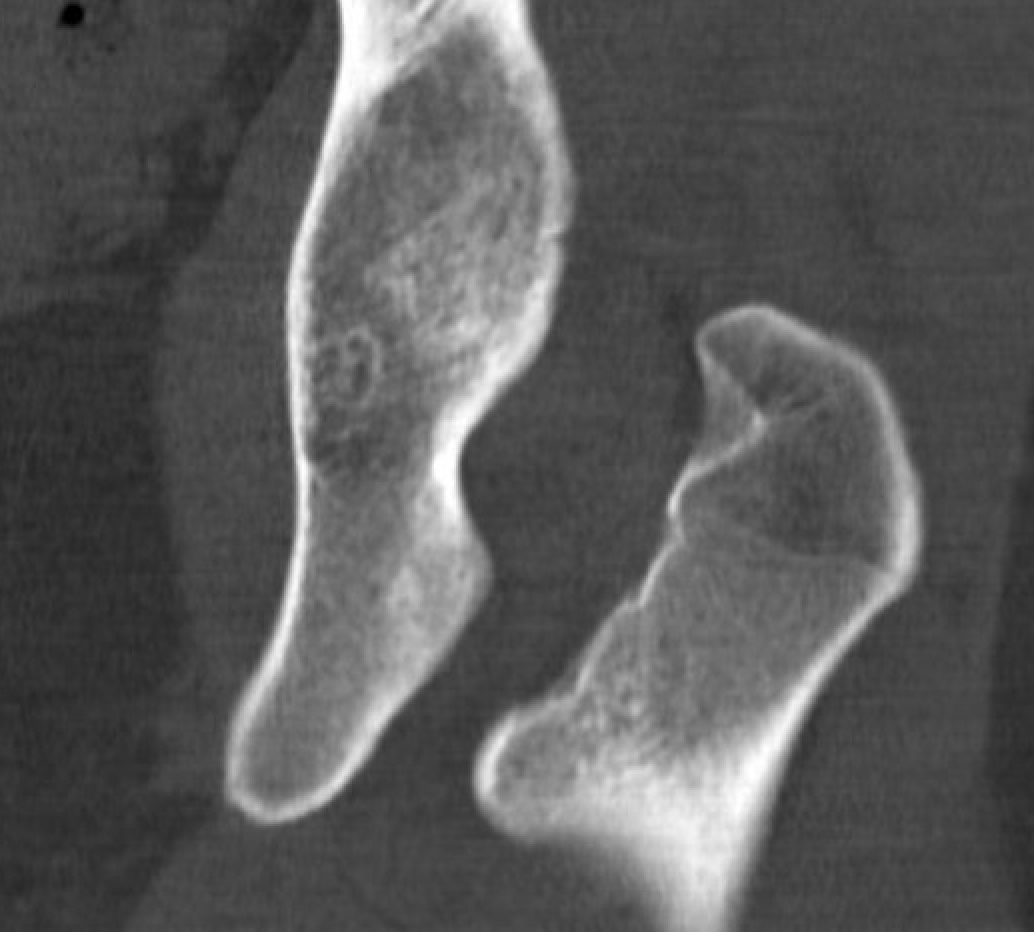

Definition

Narrowing of the ischiofemoral space between lateral ischium and lesser trochanter

Entrapment / compression of quadratus femoris

Reduced ischiofemoral space - distance between the lesser trochanter and the ischial tuberosity

Reduced quadratus femoris space - distance between hamstring tendon and iliopsoas

Inflammation / edema in quadratus femoris +/- fatty degeneration

CT